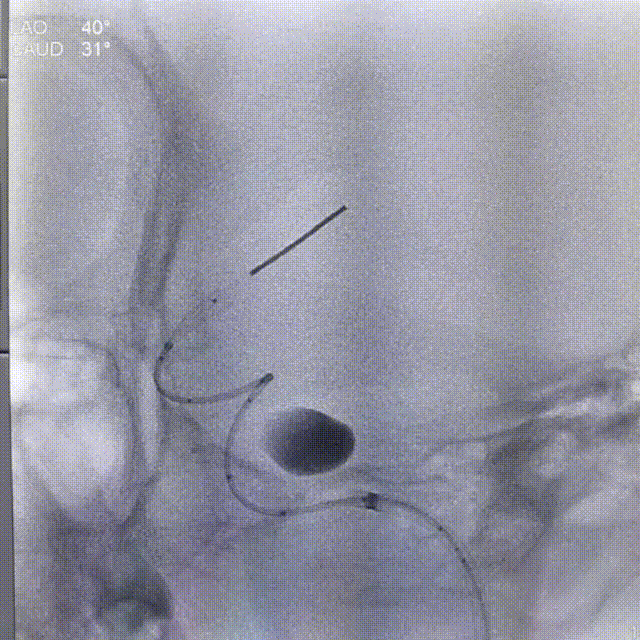

1、球囊到位,预扩张

2、微导管到位

3、第一枚Lattice输送及释放

第一枚选择的是4.4*40mm支架

4、第二枚Lattice释放

第二枚选择的是4.7*30mm支架

术后左侧颈内正侧位造影:

3、Lattice血流导向密网支架的最大优点在于其内置金属球囊支撑杆能确保支架的良好释放。

4、本例患者由于血管直径大,病变长,采用了两个较大直径支架串联的方法治疗,采用Lattice血流导向密网支架的获益就在于支架的良好打开保障了术者不需要再进行复杂的推拉和按摩操作,避免将本来就悬停在腔内的支架推挤移位,造成灾难性后果。